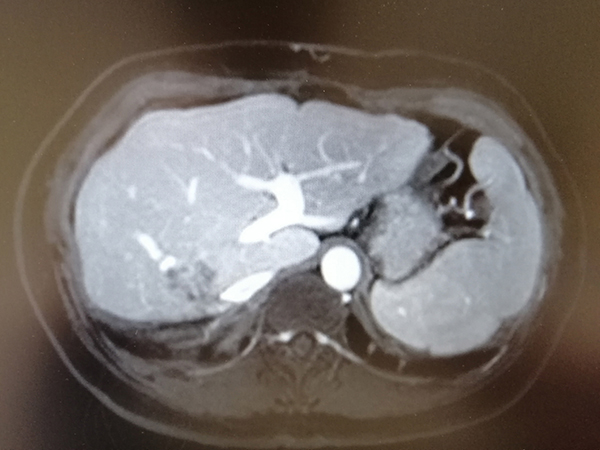

卢女士不幸罹患结肠癌,手术切除后再次发生肝内转移,经多程化疗后肿瘤明显缩小,但肿瘤靠近血管,手术切除风险大且费用较高。2020年10月28日下午,在肿瘤科主任鲁培博士的带领及李竟长副主任医师的积极协调下,肿瘤科介入团队郭旭飞副主任医师和石周主治医师经过反复讨论,并与病人深入沟通后,最终制定了肝转移瘤射频消融术的治疗方案。历时1小时,手术顺利完成,患者取得良好的治疗效果。

治疗前